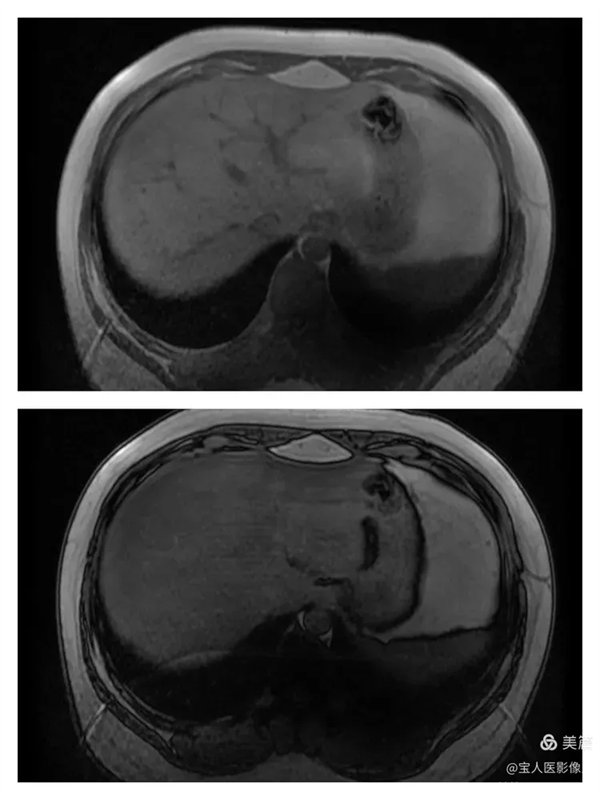

圖3

抑脂T1WI圖,軸位,肝實質(zhì)信號仍呈略低信號。

圖4

同、反相位圖,肝實質(zhì)在反相位上信號均勻降低。